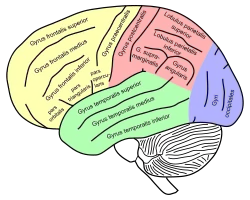

Lateral surface of left cerebral hemisphere, viewed from the side. Angular gyrus is shown in orange. Lateral view of a human brain, main gyri labeled.

Lateral view of a human brain, main gyri labeled. Cerebrum. Lateral view.Deep dissection.